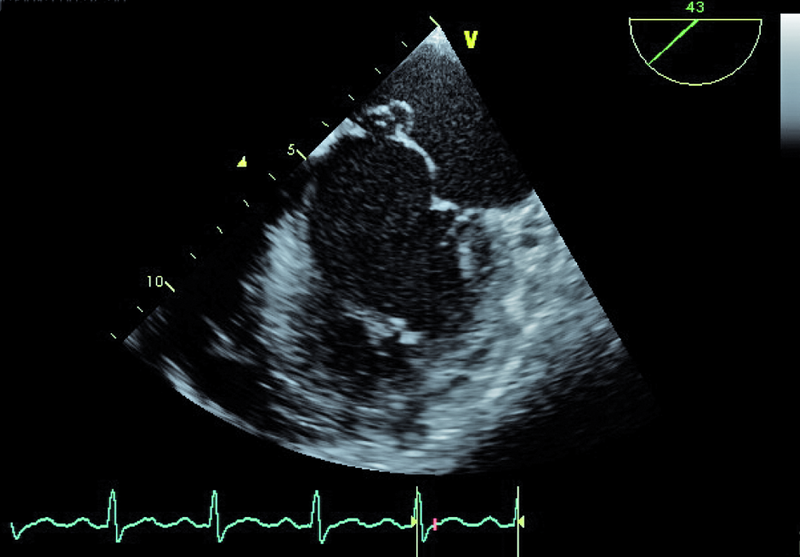

Infekcyjne zapalenie wsierdzia z zajęciem obu natywnych zastawek serca lewego nie budzi w tym przypadku wątpliwości. Proces zapalny może być rozpoznany echokardiograficznie na podstawie linijnych ech mogących odpowiadać rozerwanemu płatkowi zastawki aortalnej oraz na podstawie ciężkiego wypadania płatka zastawki mitralnej (flail), mającego zapewne charakter poinfekcyjny (ryc. 1). Stopień destrukcji zastawki mitralnej w porównaniu z zastawką aortalną wydaje się większy. Między segmentami A2 i P3 pojawia się tętniakowate uwypuklenie, będące pozostałością nacieczenia zapalnego i martwicy tkanki (ryc. 2). Tryb kolorowego doplera ujawnia dwa strumienie niedomykalności – jeden, ekscentryczny wynikający z wypadania przedniego płatka i biegnący wzdłuż bocznej ściany przedsionka (ryc. 3), i drugi pojawiający się w pewnej odległości od miejsca koaptacji, w miejscu, w którym fali zwrotnej trudno się spodziewać, jeśli struktura tkanki budującej płatek jest nienaruszona (ryc. 3, 4). Strumień niedomykalności mitralnej ma w tym wypadku charakter ostry i trafia do nieprzygotowanej i niepowiększonej jamy lewego przedsionka (ryc. 3, 4). Umiarkowana dotychczas niedomykalność aortalna, którą chory przez wiele lat dobrze tolerował, się nasiliła. Dowodem na to jest krótki czas spadku gradientu ciśnień aorta – lewa komora (poniżej 200 ms) (ryc. 5) oraz wyraźny sygnał wsteczny holodiastoliczny w aorcie zstępującej, świadczący o wysokiej wartości frakcji niedomykalności aortalnej (iloraz całki prędkości wypływu krwi na obwód i prędkości fali wstecznej 83%!) (ryc. 6).